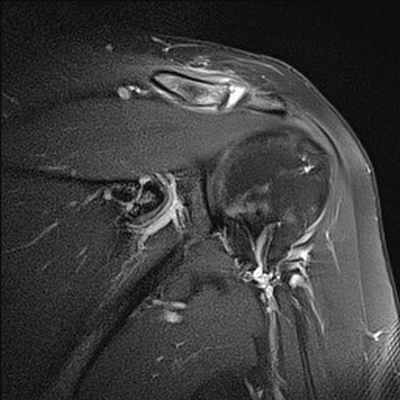

МРТ плечевого сустава

Плечелопаточный периартрит (периартроз, периартикулярные поражения области плечевого сустава) - собирательный термин всех периартикулярных поражений области плечевого сустава. Нередко боли в области плечевого сустава вызваны не поражением самого сустава, а околосуставных мягких тканей. Наиболее частой причиной острой или хронической боли в области плечевого сустава является дегенеративно-воспалительное поражение сухожилий мышц, участвующих в движениях плеча (тендиниты). От чрезмерной физической нагрузки (у маляров, спортсменов и людей других профессий) сухожильные волокна растягиваются и надрываются. В конечном итоге развивается воспалительный процесс. Острый период с резкими болевыми ощущениями у таких пациентов длится обычно несколько недель, и при эффективном лечении интенсивность болей в плече снижается, функция сустава восстанавливается. Однако благоприятное течение заболевания с полным выздоровлением заканчивается далеко не у всех. У многих больных при неблагоприятном развитии патологического процесса боли в плече не проходят, а подчас усиливаются не только при физической нагрузке, но и в покое, приобретают постоянный характер. Движения в суставе, как правило, сопровождаются хрустом различной интенсивности. В далеко зашедших случаях может возникнуть тугоподвижность сустава, атрофия мышц и остеопороз головки плечевой кости. При рентгеновском исследовании чаще всего определяется кальцификация (отложение солей) в суставных сумках и в окружающих сустав тканях. МРТ дает полную картину патологических изменений в периартикулярных тканях на ранних этапах заболевания - это отек в области сухожилий, их истончение или неполный разрыв, наличие выпота в суставных синовиальных сумках, атрофия отдельных групп мышц и др. Среди основных показаний к МРТ исследованию плечевого сустава являются нестабильности в суставе и разрывы вращательной манжеты плеча.

Нестабильность плечевого сустава отмечается при слабой фиксации головки плечевой кости в суставной впадине лопатки, которая приводит к повышенной подвижности в суставе и часто к развитию вывихов и подвывихов при травмах, определенных положениях руки (например, при бросании предметов из-за головы вперед). Если диагностика вывихов не представляет особых затруднений при обычном рентгенологическом исследовании, то подвывихи не всегда четко визуализируются при данном методе лучевой диагностики. МРТ диагностика в этих случаях позволяет визуализировать даже незначительные нарушения взаимоотношений головки плечевой кости и суставной впадины лопатки.

Разрывы вращательной манжеты плеча являются наиболее частой причиной болевого синдрома в плечевом суставе во всех возрастных группах взрослого населения и невозможности поднять или отвести руку. МРТ диагностика при данной травме позволяет визуализировать как полный разрыв связок, так и частичное их повреждение. Как правило, сопутствующими осложнениями повреждений вращательной манжеты плеча является скопление жидкости в субакромиальной и поддельтовидной сумках (находятся между мышцами), что также хорошо выявляется при МРТ исследовании. А восстановление разрыва сухожилий вращательной манжеты является сложной хирургической операцией.

МРТ признаки повреждения акромиально-ключичного сочленения на уровне плечевого сустава